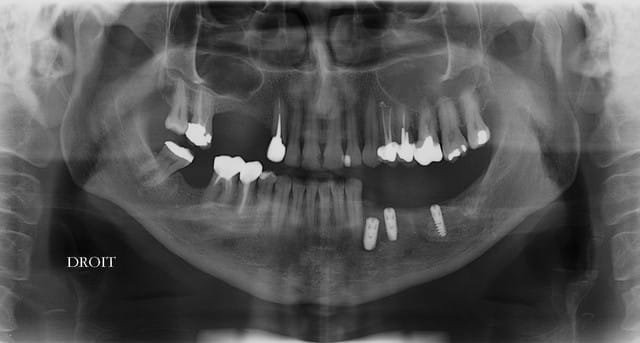

Par contre, la réhabilitation du secteur 3 semble "curieuse''

Effectivement le secteur 3 est curieux radiologiquement mais il y a des raisons ... l'expansion à la mandibule, fut...sportive.

Pour l implant sur 14 il manque de l os en vestibulaire? Mise en place d os synthetique et membrane ou prelevement ramique?

Pour la 16 , une augmentation par abord lateral ou orthograde( desole je me souviens plus du nom de la technique).

Bonjour, pour la 16 ,tu peux faire une ostéotomie de SUmmers, tu as plus de 4 mm d'os .

Un implant de 10 mm devrait suffir.

Pour la 12 ou 13 utilise les expanseurs, prévoit un 3,6